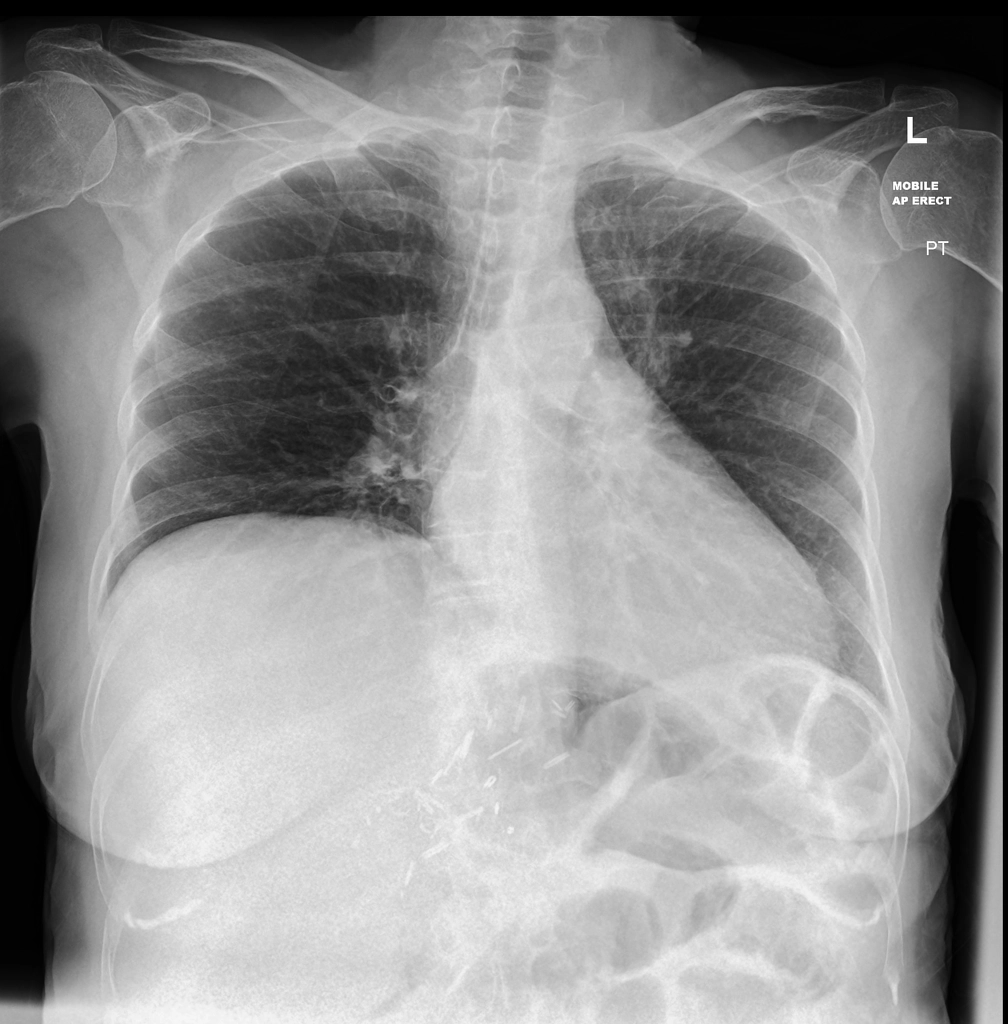

Pneumonia  ?